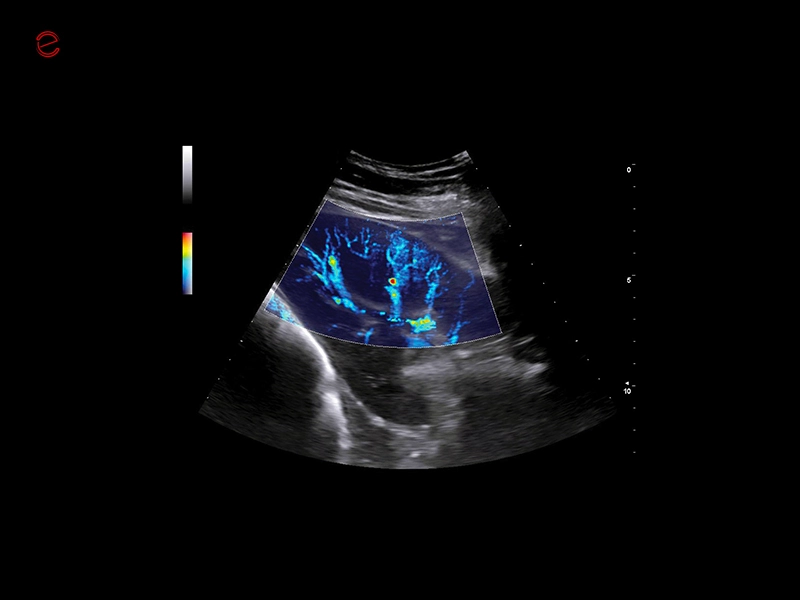

HIGH-RESOLUTION IMAGING IN ALL APPLICATIONS

Unmatched vision

Herons have exceptional eyesight, enabling them to detect subtle movements even in challenging conditions, making them highly effective hunters. Similarly, MyLab™Heron offers incredibly detailed and high-resolution imaging, in superficial areas as well as in deeper ones, thanks to the wide range of probes. All this makes it possible to scan from the smallest to the biggest animals in all applications covering general imaging, cardiology, musculoskeletal, reproduction, and ensuring unmatched clarity in all your examinations.